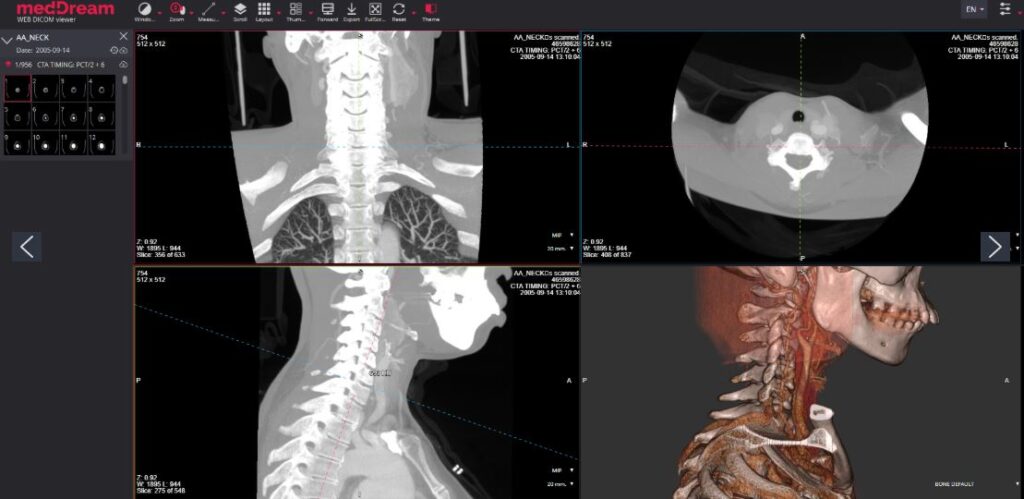

Dr. Francis Christensen

DICOM 3.0 compliant picture archiving and communication system. The PACS server provides connectivity to all DICOM modalities (CR, DX, CT, MR, US, XA, etc.). Review of DICOM images and diagnostics can be done using the MedDream WEB DICOM Viewer.Go to SitePad Editor to add your own text and edit me. It’s easy. Just Go to SitePad Editor to add your own text and edit me content and make changes to the font.